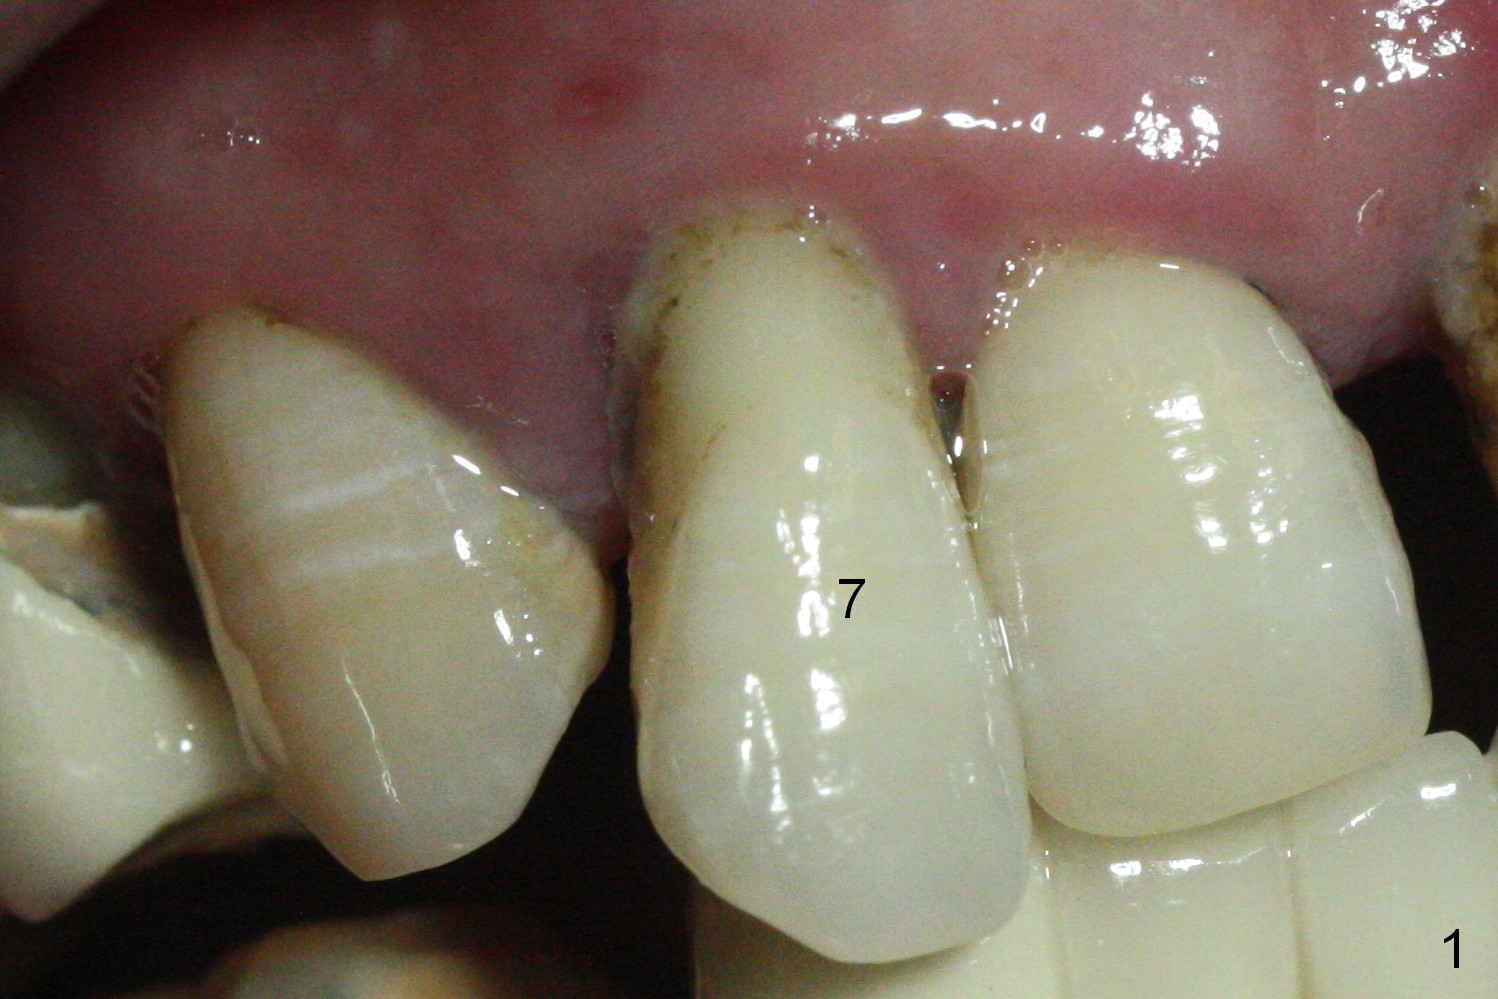

After extraction of the labioincisally displaced #7 (Fig.1, Metronidazole), place either 1 or 2- (Fig.2) piece implant. For the latter (bone density 200-800 units), prepare cemented or angled abutments with 5 mm cuff. Use a crown form for provisional (single unit).

In fact the buccal plate feels to be perforated when 2 mm initial drill is being used probably at the deepest area of the concavity shown in Fig.2 (near B). The trajectory is adjusted and the osteotomy is enlarged by 3 mm drill for 13 mm (Fig.3). When a 3.8x13 mm implant is placed (50 Ncm), an angled abutment is used (Fig.4, 4.5x15°(A)5 mm). As planned, a 3.8x13 mm implant is placed at #13, while bone graft is placed mesial and palatal to #15 implant. No provisional is fabricated from #9 to 15 due to time limitation and lack of parallism between the abutments.